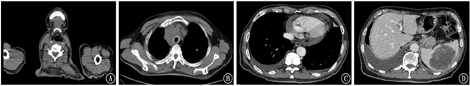

入院完善相关检查。胸腹部CT(2018年5月4日)提示:纵隔、右侧锁骨上窝、腹膜后、盆腔右侧及右侧腹股沟区多发肿大淋巴结,双肺多发结节,脾脏多发占位,考虑恶性肿瘤性病变,淋巴瘤可能性大,请结合临床;其中纵隔病灶侵犯上腔静脉、气管及支气管。左肺少许炎症。双肺胸腔少量积液,双肺下叶局部膨胀不全。心包少量积液。考虑左侧声带麻痹可能性大,建议必要时进一步检查(图1)。右锁骨上淋巴结活检免疫组织化学:CK(-),EMA(-),CD20(+++),CD3(-),CD5(-),CD22(+++),Ki67(几乎100%+),EBERs(-),CD23(-),CD10(-),CD21(肿瘤细胞弱阳性),ALK(5A4)(-),Bcl6(+++),CD138(-),MUMI(+++),Bcl2(-),Cyclin D1(-),Cmyc(70%+)。病理诊断:(右锁骨上淋巴结)非霍奇金淋巴瘤,弥漫大B细胞淋巴瘤,间变亚型,非生发中心B细胞样型免疫表型亚群。结合患者其他检查结果,患者诊断为:非霍奇金淋巴瘤(弥漫大B细胞型,ⅣB期,IPI 4分)。